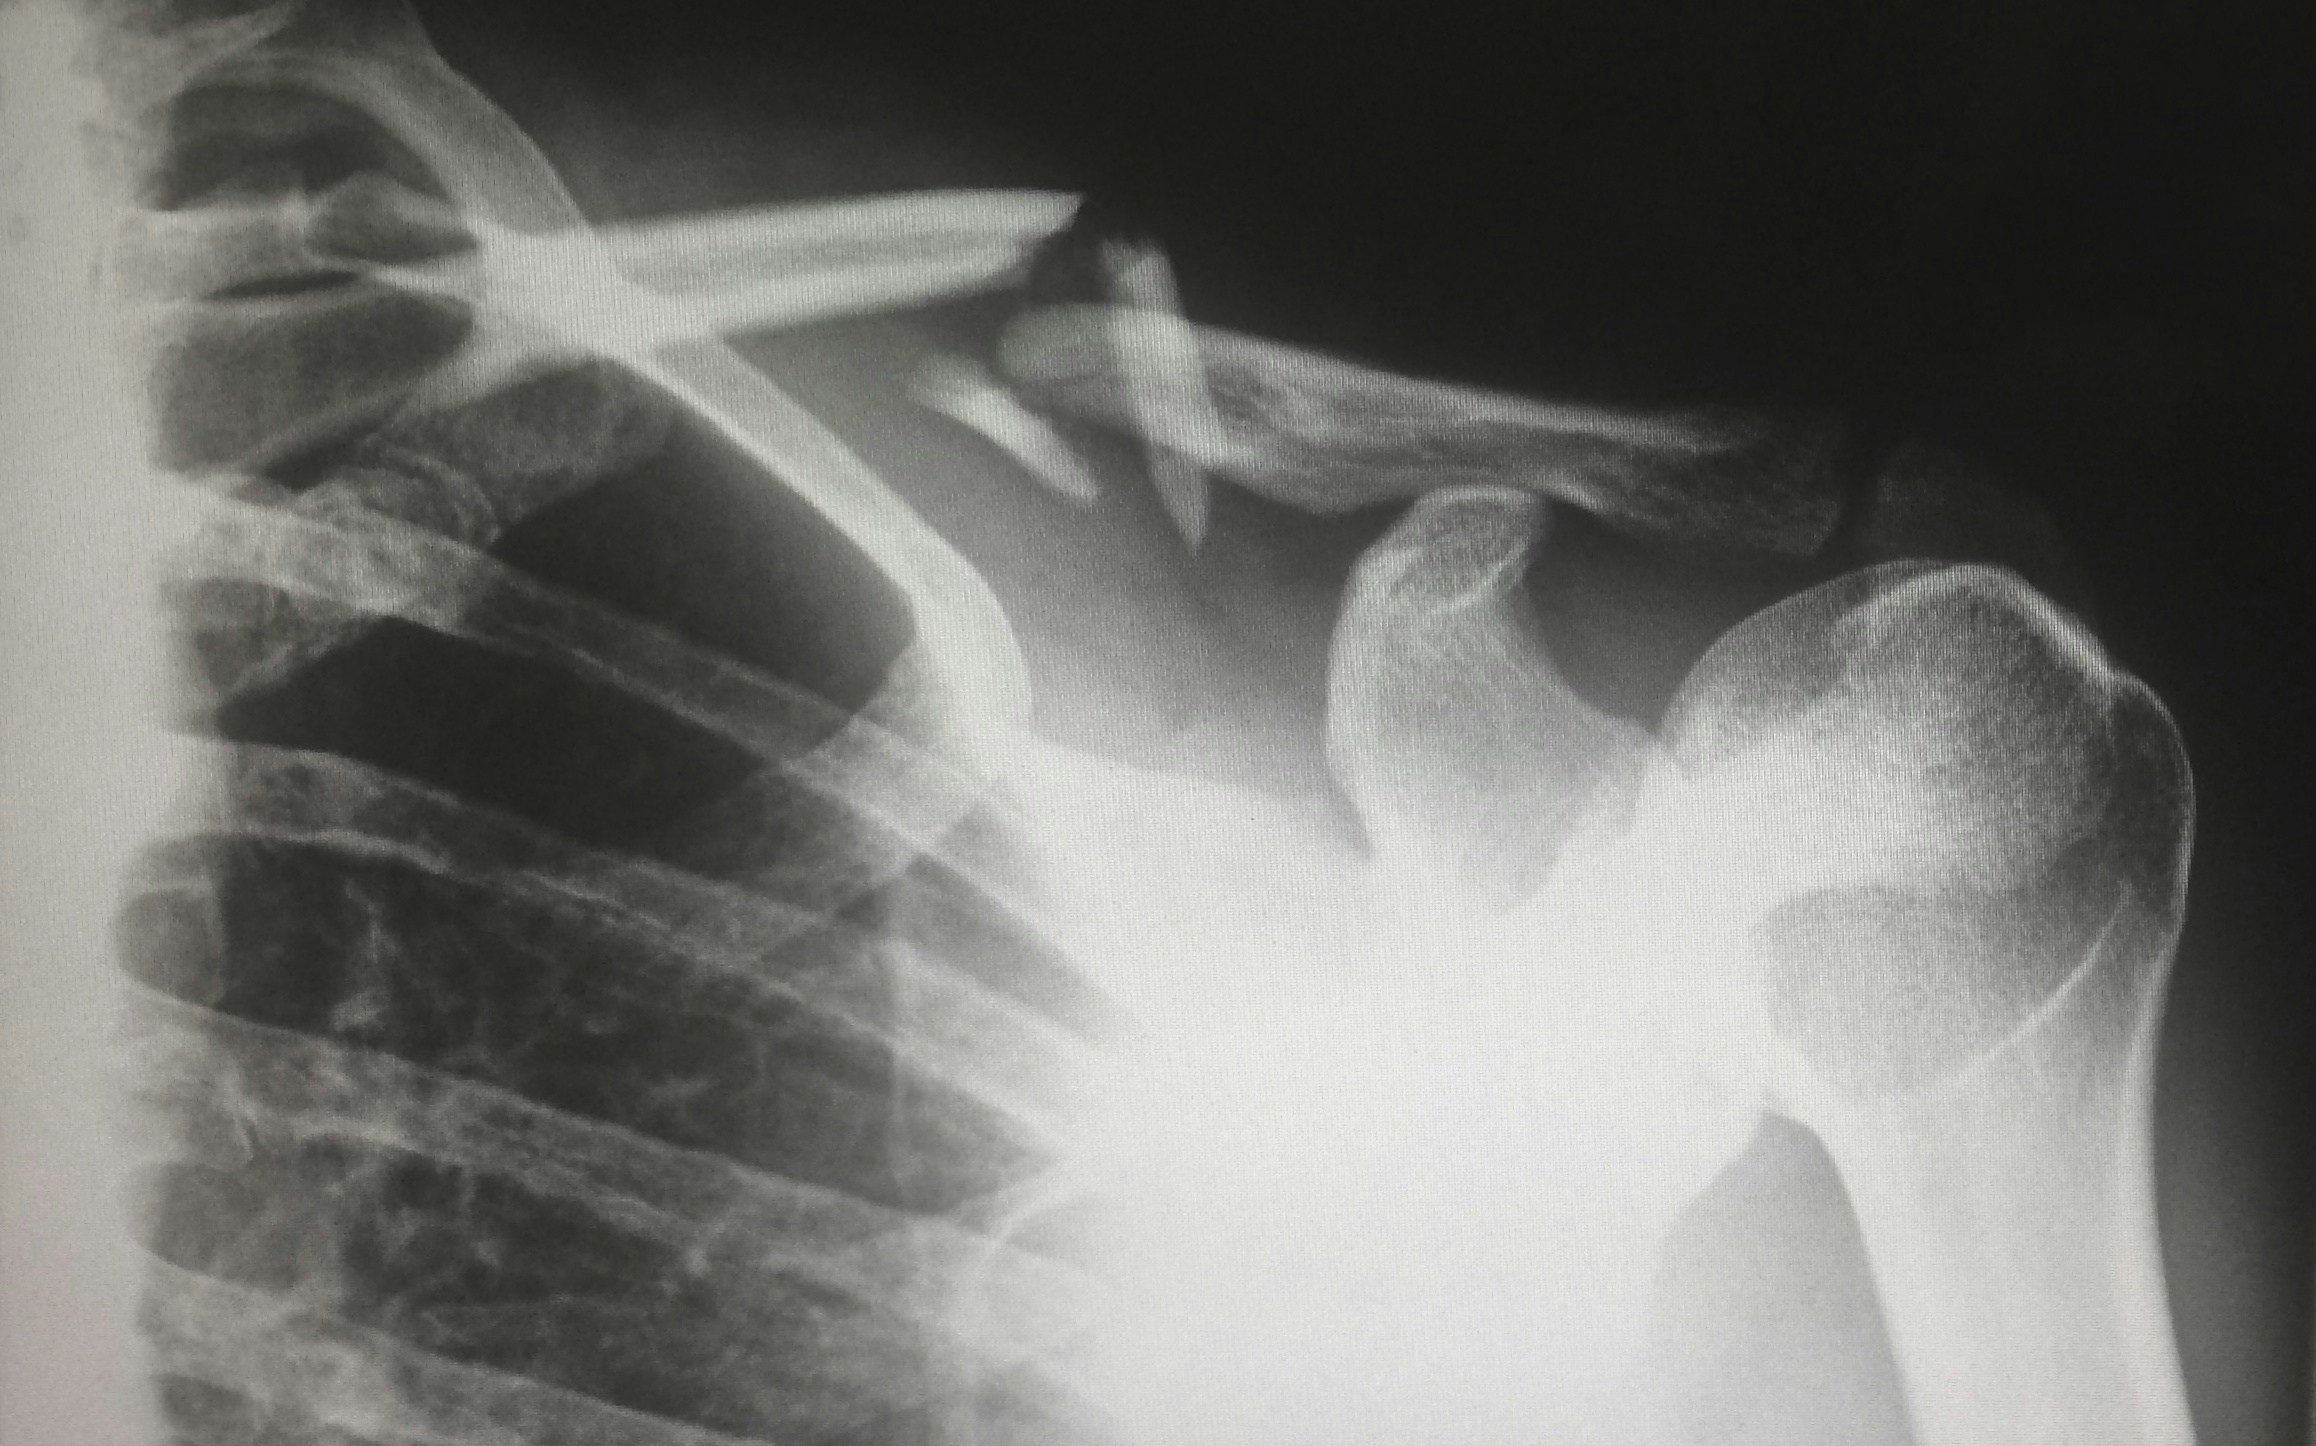

골다공증을 진단하기 위해 가장 널리 사용되는 방법은 골밀도 검사입니다. 이 검사는 X선을 이용하여 뼈의 밀도를 측정하며, 골다공증의 유무와 진행 정도를 파악하는 데 유용합니다. 특히 폐경 후 여성, 60세 이상 남성, 그리고 이전에 골절을 경험한 사람들은 정기적인 골밀도 검사를 받아야 합니다.

영상 검사를 통해 척추, 고관절, 손목 등 주요 부위의 뼈 상태를 상세히 살펴볼 수 있습니다. 정확한 진단은 적절한 치료와 예방 전략 수립에 필수적이므로 증상이 의심될 경우 빠르게 검사를 받는 것이 중요합니다.

골다공증으로 인한 주요 합병증은 골절입니다. 척추, 고관절, 손목은 골다공증으로 인해 가장 흔히 손상되는 부위입니다. 특히 고관절 골절은 노년층 환자의 경우 회복이 어려워 사망률 증가로 이어질 수 있습니다. 골절을 예방하려면 낙상 방지가 필수적입니다. 집안의 미끄러운 바닥을 제거하고, 안정적인 신발을 착용하며, 계단을 오르내릴 때 주의해야 합니다.